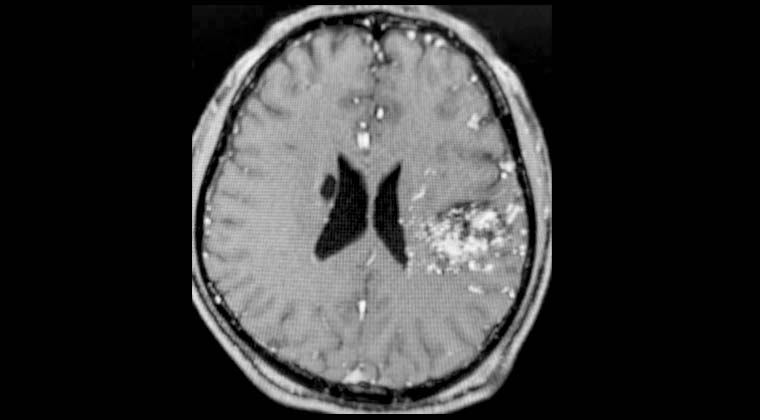

② Случай 2:

Пациентка: женщина, 56 лет

Жалобы: слабость в левой стороне тела, нарушение походки в течение 2 недель. Диагноз: множественные метастазы рака легких в головной мозг.

Рисунок 1: 25.02.2022 Планирование лечения Гамма-ножом опухоли в правой лобной доле, выраженный перифокальный отёк.

Рисунок 2: 25.02.2022 Одновременно проведено лечение Гамма-ножом опухоли в левой височной доле.